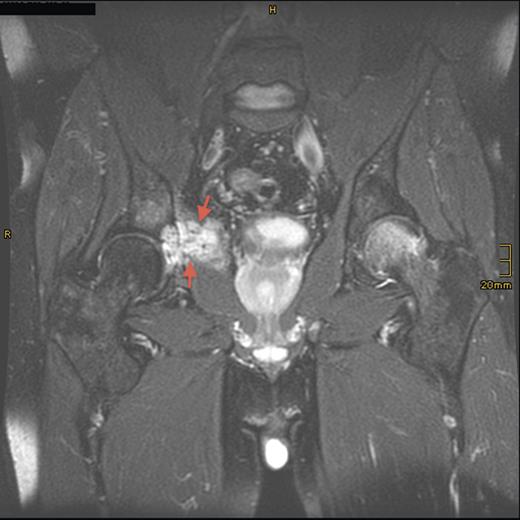

Magnetic resonance imaging (MRI) and computed tomography (CT) scanning showed a destructive lesion, 5 cm in diameter, in the right os ilium and obturator internus muscle (Fig. 1). FGF-23 levels were significantly high and an octreotide scan was positive for radionuclide uptake in the right acetabulum. CT-observed biopsy of the right acetabulum was performed, and histological analysis revealed a benign phosphaturic tumor (PHT) of mixed connective tissue type.

Sagittal T2-weighted, fat-suppressed contrast-enhanced MRI demonstrating the tumor lesion (5 cm in diameter) in the right acetabulum (arrows) 8 years prior to presentation.